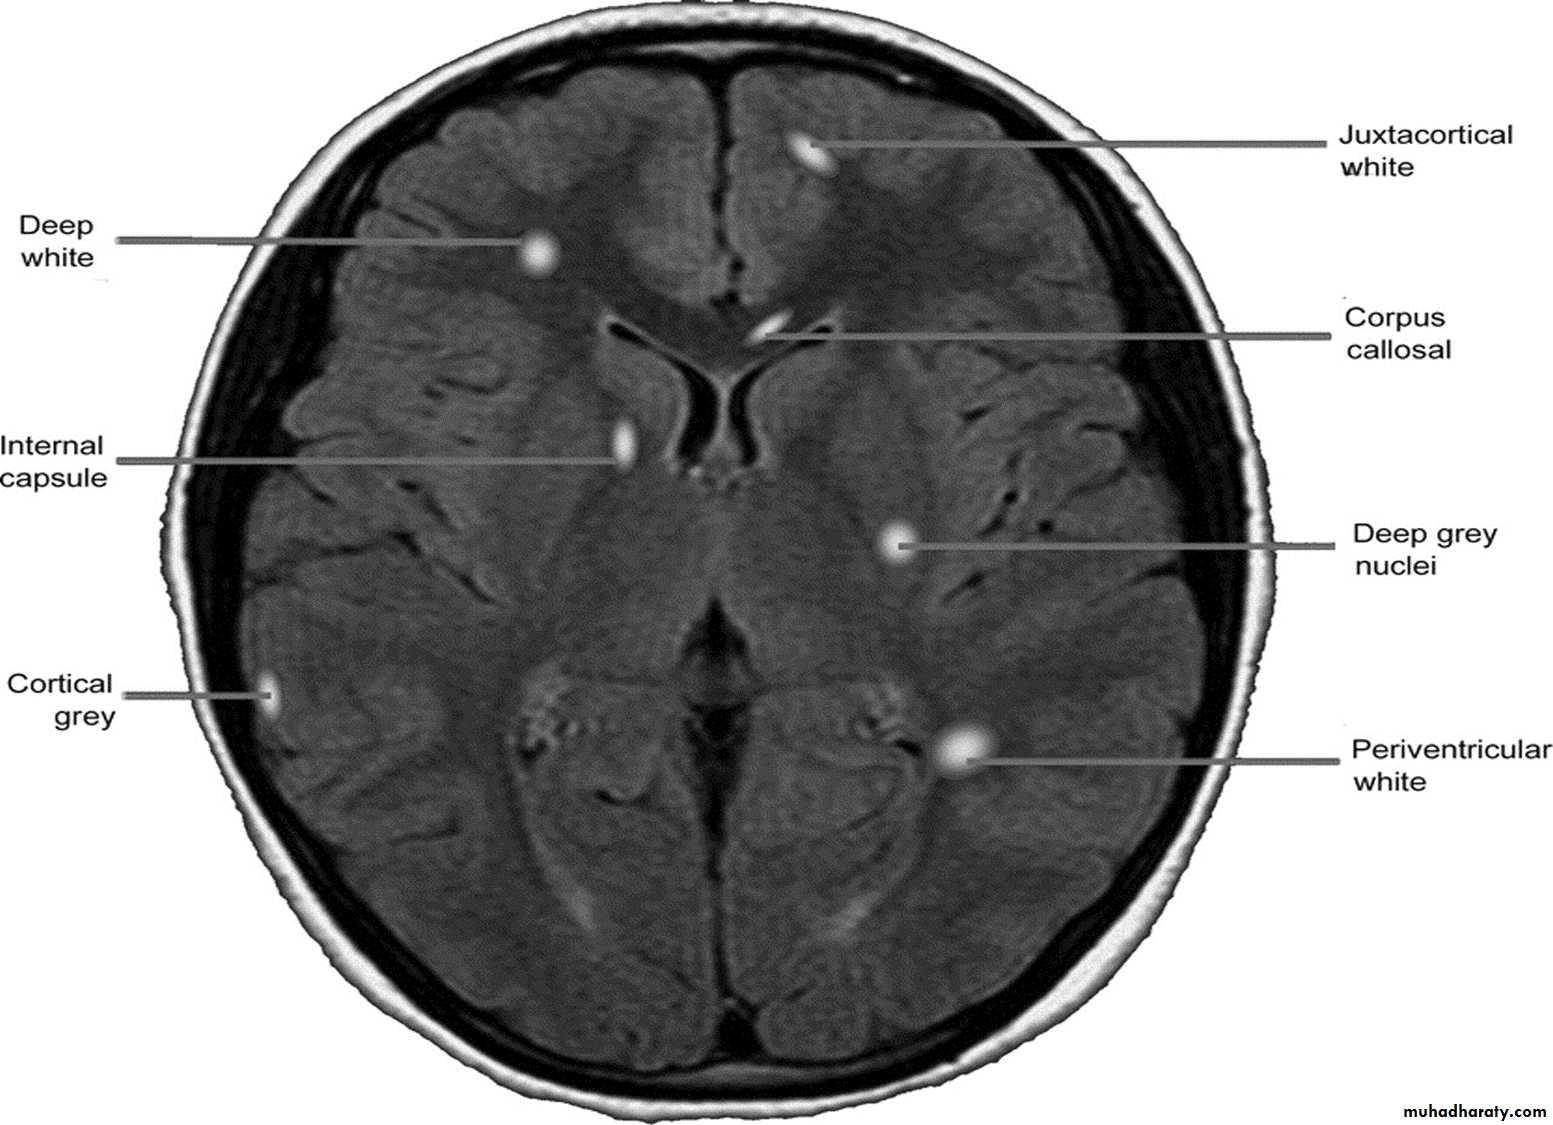

MRI :characteristic abnormalities are found in >95% of patients, although more than 90% of the lesions visualized by MRI are asymptomatic

Lesions are frequently oriented perpendicular to the ventricular surface,(Dawson’s fingers)

Lesions larger than 6 mm located in the corpus callosum, periventricular white matter, brainstem, cerebellum, or spinal cord are particularly helpful diagnostically

There is no definitive diagnostic test for MS. Diagnostic criteria for clinically definite MS require documentation of two or more episodes of symptoms and two or more signs that reflect pathology in anatomically noncontiguous white matter tracts of the CNS